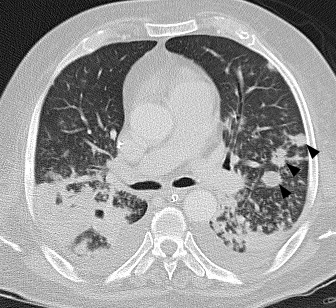

Paciente masculino de 70 años de edad con EPS asociada a artritis de cadera derecha por Staphylococcus aureus meticilino-resistente.La embolia pulmonar séptica (EPS) se define como la presencia de trombos sépticos en la circulación pulmonar provenientes de un foco infeccioso extrapulmonar. La obstrucción del flujo en vasos de pequeño calibre (secundaria a la presencia de émbolos infecciosos en la luz del vaso), puede condicionar el desarrollo de infartos y abscesos pulmonares.Las entidades asociadas a EPS son de naturaleza variada e incluyen: infecciones asociadas a dispositivos intravasculares, endocarditis infecciosa, abscesos hepáticos, infecciones en piel y tejidos blandos, tromboflebitis séptica, síndrome de Lemierre e infección periodontal. Los microorganismos aislados con mayor frecuencia son: cocos gram positivos (Staphylococcus aureus, Staphylococcus coagulasa negativo, Streptococcus spp.) y bacilos gram negativos (Fusobacterium, Klebsiella pneumoniae).Las manifestaciones clínicas de EPS son inespecíficas (fiebre, disnea, tos, dolor torácico pleurítico y hemoptisis).Las alteraciones en los estudios de imágenes son esenciales en el diagnóstico de EPS.En la radiografía de tórax de pacientes con EPS se describen opacidades nodulares, consolidación, lesiones cavitadas y derrame pleural.La tomografía computarizada (TC) es la imagen de mayor utilidad en la valoración de pacientes con sospecha de EPS. Las manifestaciones de EPS en TC se describen en la Tabla 1.